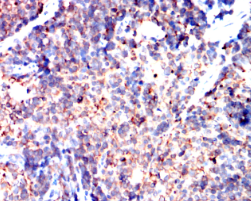

PIK3CA Mouse Monoclonal antibody[4F3A6]

PIK3CA is the most mutated gene in breast cancer and is important in other cancers. An integral part of the PI3K pathway, PIK3CA is an oncogene with two hotspots for activating mutations: the 542/545 region of the helical domain and the 1047 region of the kinase domain. The interaction of PIK3CA with the AKT and mTOR pathways is the subject of an immense amount of research and development, and PI3K inhibitors have exhibited some success in recent clinical trials. While PI3K monotherapies are likely insufficient, there is interest in pursuing PI3K inhibition in combination with other therapies including TKI's, MEK inhibitors, PARP inhibitors, and - in breast cancer - aromatase inhibitors.

IHC    1/200 - 1/1000